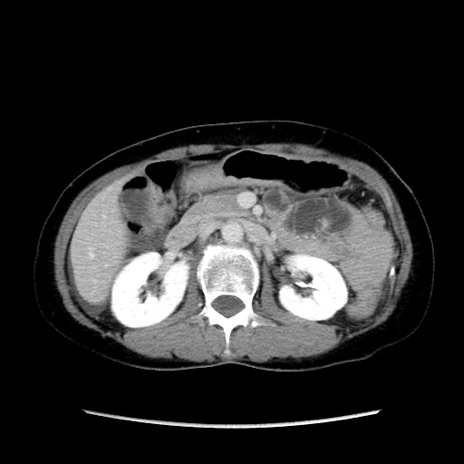

症例32(横断像)

【症例】40歳代 女性

【主訴】上腹部痛、嘔気・嘔吐

【現病歴】約9時間前頃から急に上腹部痛、嘔気、嘔吐が出現。改善しないため救急要請。

【データ】WBC 8400、CRP 0.03